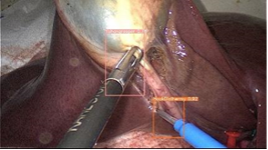

Situation Awareness for Automated Surgical Check-listing 2: 2D detection of surgical instruments from the wearable camera and laparoscopic video |

Situation Awareness for Automated Surgical Check-listing 3: Surgical phase segmentation |